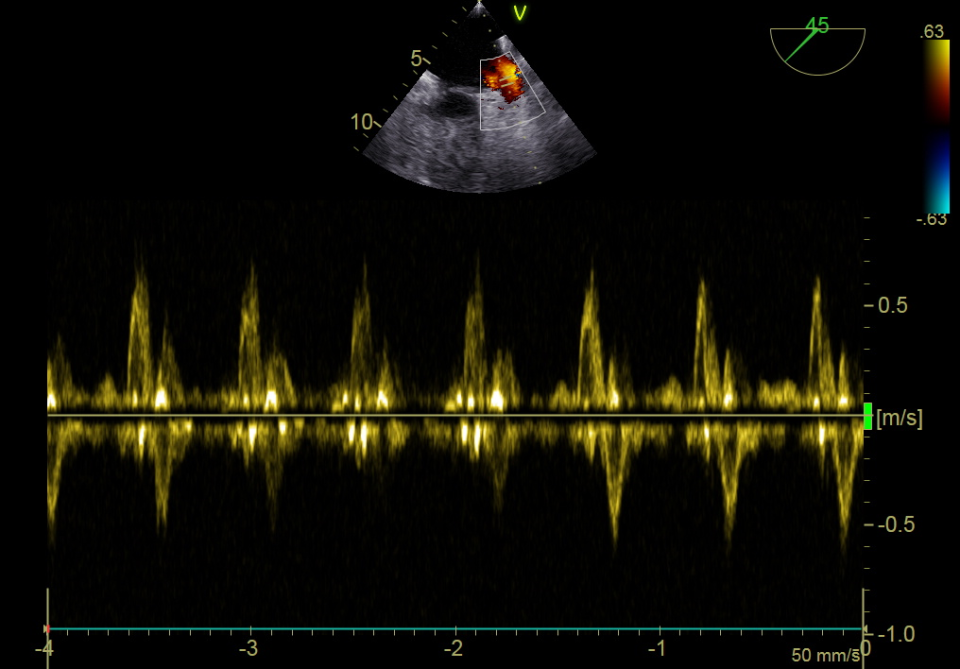

a) 经食管超声心动图(tee),带和不带彩色多普勒,2b型,指状动脉导管未

图片尺寸737x641